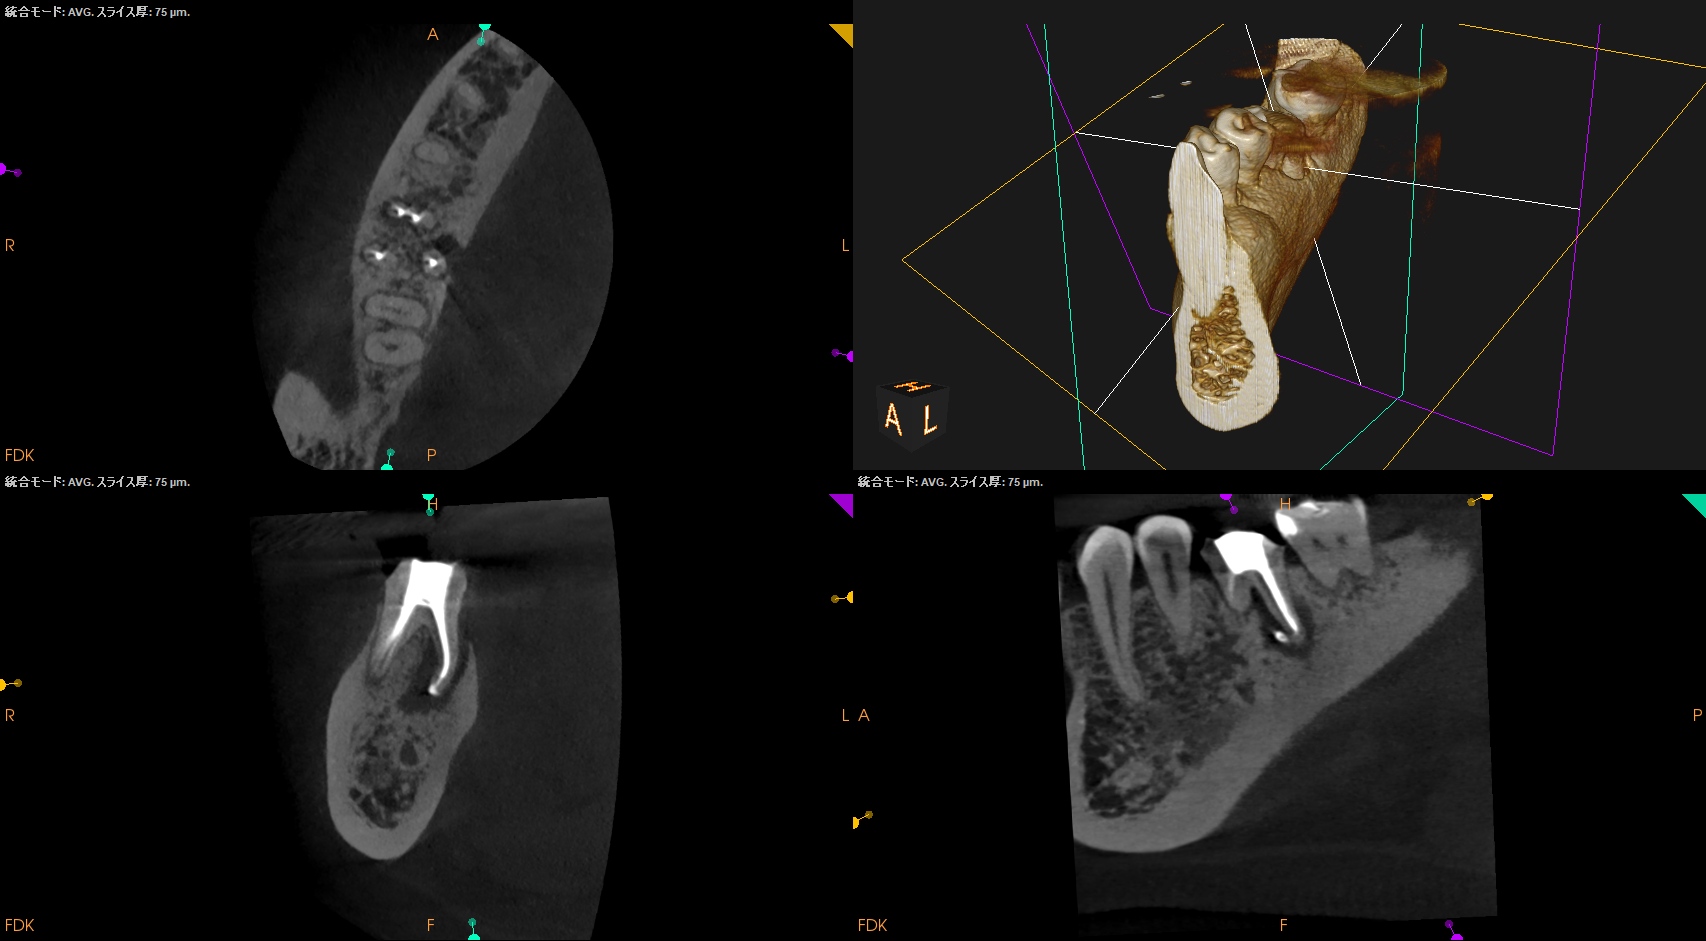

#30 Re-RCT 1yr recall(2026.3.10)

MB

ML

D

Radix

初診時と比較した。

病変は完治した。

このことから最終補綴もOKだし、経過観察も終診とさせていただいた。